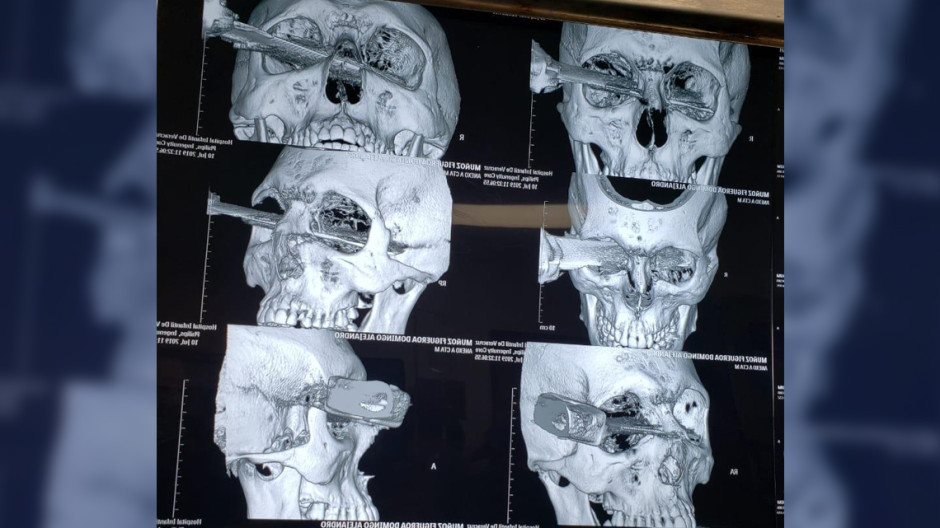

El herido fue trasladado al Hospital General de Veracruz donde médicos especialistas retiraron quirúrgicamente el cuchillo del ojo del paciente. En las radiografías se puede observar el arma atravesada en el cráneo, el cuchillo entró por el ojo izquierdo, atravesó la nariz y alcanzó la cuenca del ojo derecho.

Familiares del paciente confirmaron que éste perdió el ojo tras la cirugía. Por su parte, el agresor fue detenido y trasladado por la Policía Naval.